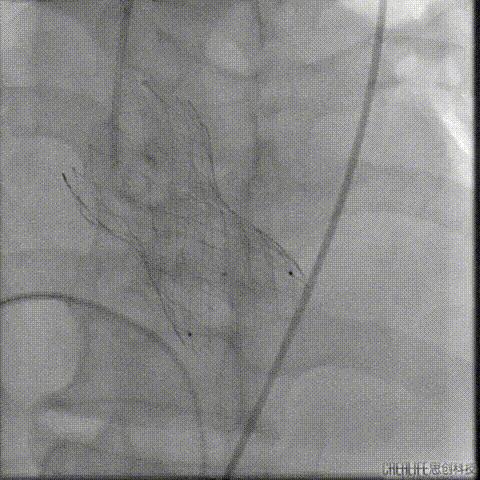

经桡冠脉保护

置入Venus-A32号瓣膜并释放

复查造影

撤出冠脉保护

再次复查造影